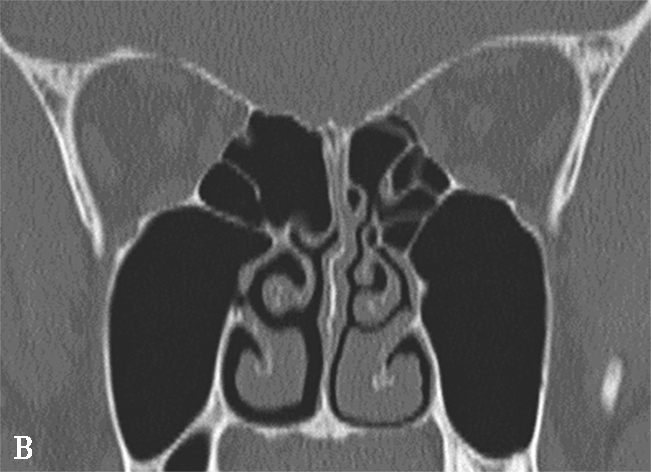

窦口鼻道复合体(ostiomeatal complex,OMC):由于纤维内镜生理性手术的需要,近一二十年来提出了窦口鼻道复合体的概念。窦口鼻道复合体并非一个独立的解剖结构,而是指前组鼻窦自然开口周围的区域,包括中鼻甲、钩突、半月裂、筛漏斗、鼻丘、筛泡、上颌窦自然开口等解剖结构(图1-3-2)。

图1-3-2 窦口鼻道复合体解剖

1.半月裂;2.钩突;3.中鼻道;4.筛大泡;5.筛漏斗;6.上颌窦开口